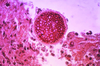

How does Pneumocystis pneumonia appear on methanamine-stained samples?

Disc-shaped yeasts

What disease is caused by Pneumocystis jirovecii?

Pneumocystis pneumonia (PCP), which is a diffuse interstitial pneumonia

How is Pneumocystis pneumonia diagnosed?

From a bronchoalveolar lavage or lung biopsy; sample stained with methenamine silver or identified with a fluorescent antibody